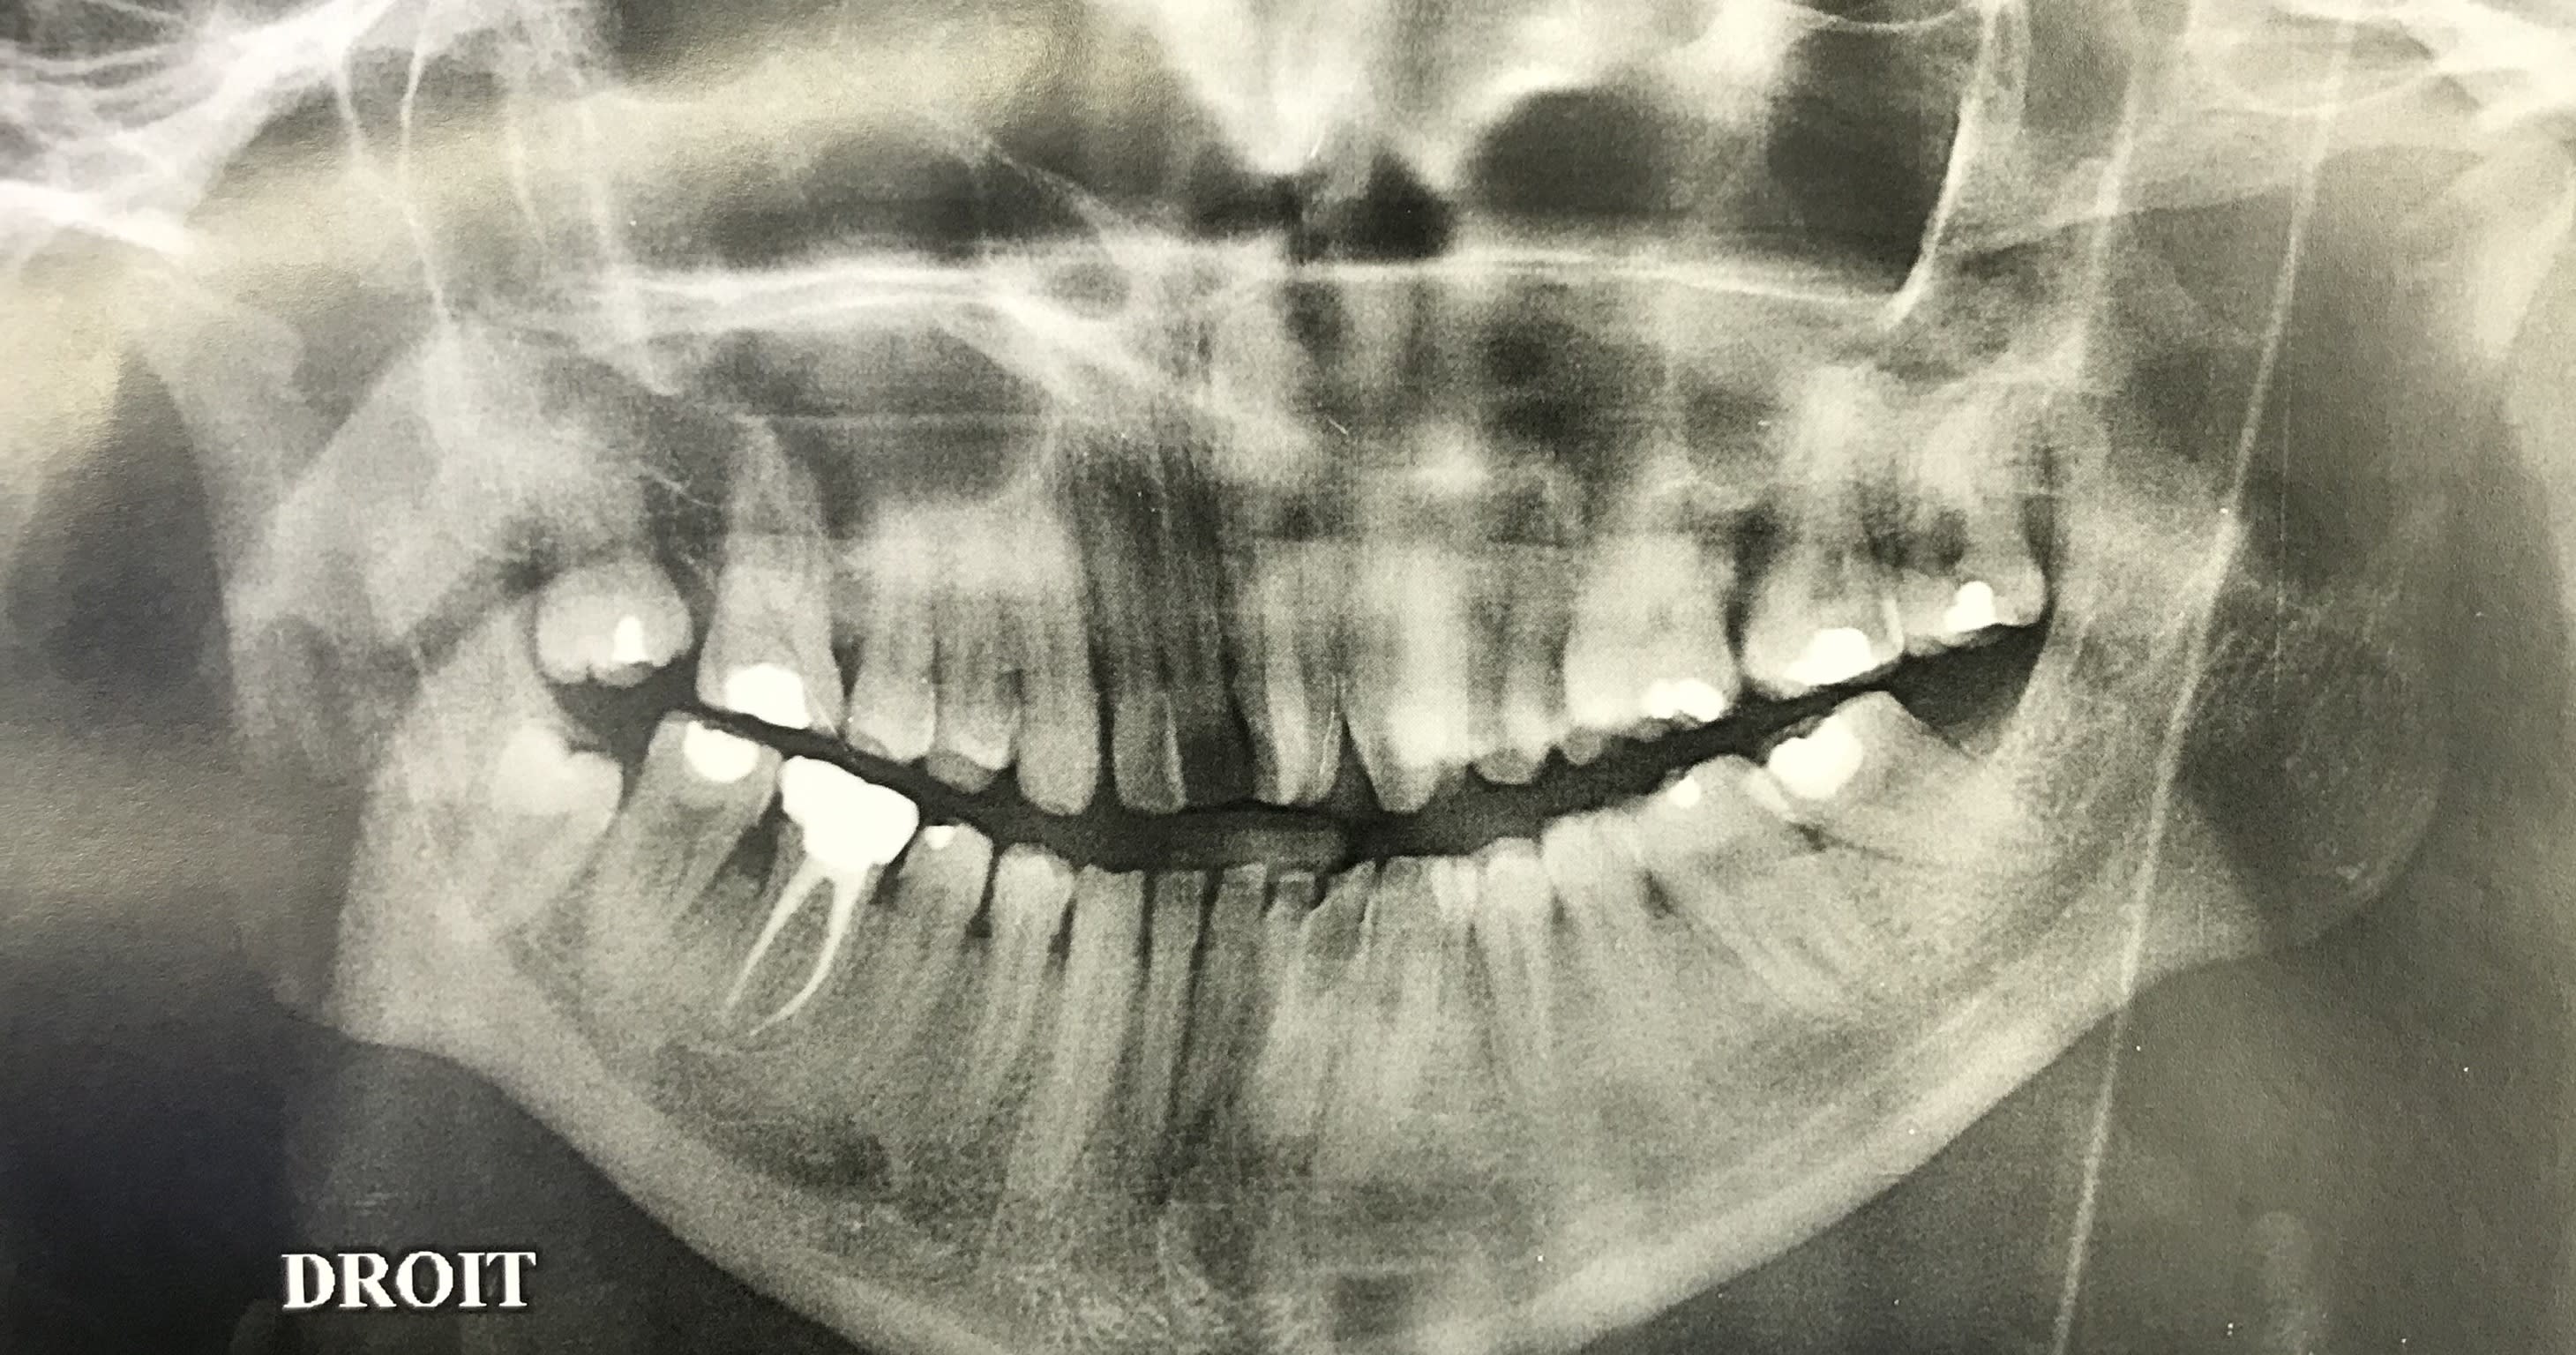

En attendant que le nouveau réponde ... Dans un style différent : 38 ans . très complexé. Aucun dentiste n’a voulu le toucher (pour le secteur antérieur) . Je lui ai dit qu’il fallait lui déglinguer la mâchoire. Sauf qu’il ne veut pas faire de chirurgie orthognatique, c’est sa seule condition . Par contre est prêt à mettre n’importe quel prix pour retrouver un beau sourire. N’est ni fermé à l’ortho , ni fermé à l’implantologie.

Photo de la pano qu’il m’a ramenée.

On se passera des : faut faire un détartrage :) , ou faut qu’il se lave les dents.

Le cas du début c'est avant tout une supraclusie carabinée.